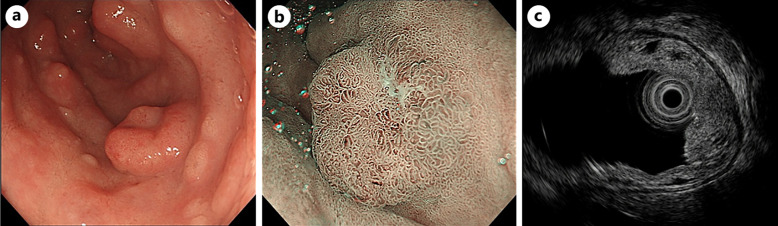

Case presentation: A 52-year-old woman was referred for a duodenal polyp. Endoscopy revealed multiple duodenal bulb polyps suggestive of Brunner's gland hyperplasia. Histopathology confirmed well-differentiated tubular adenocarcinoma with submucosal invasion and a positive margin. The patient underwent pancreaticoduodenectomy, and residual subserosal carcinoma was detected. Despite adjuvant chemotherapy, liver metastases and peritoneal dissemination developed 7 months postoperatively. The patient died 24 months after surgery.